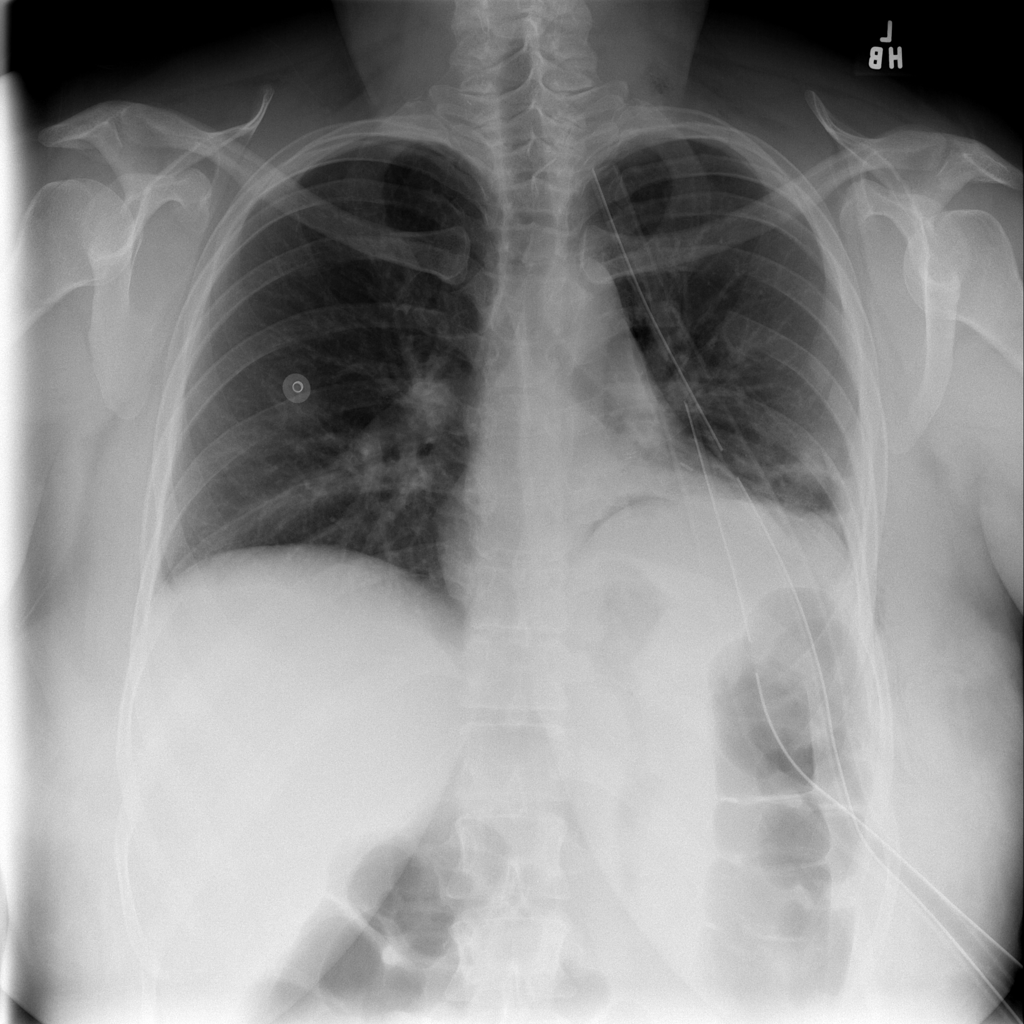

PAT-894B · IMG-000Emphysema

PAT-894B · IMG-000

PA